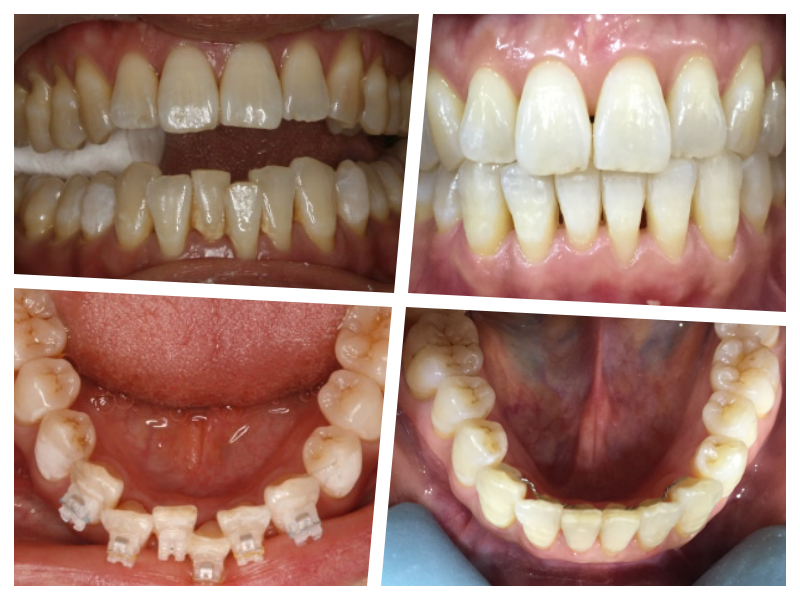

40대 고등학교 선생님, 최근 더 아래 앞니가 신경 쓰인다고..

전체 교정을 다해서 어금니 교합도 더 맞추고 앞니 수직수평피개까지 맞추면 더 좋지만 먹고 마시고 말하고 일상생활에 전혀 문제가 없는경우 불편한 부위만 해소해 주는 것이 좋다고 생각한다.

대략 8개월의 교정기간과 현재 5년간 잘 유지 중이다.